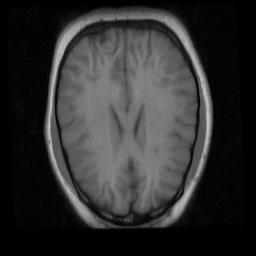

Refer to caption

Figure 10: Illustration of the brain registration performance of the proposed unsupervised methods with and without mask: (a), (c), (e) , (g), (i) and (k) respectively denote the moving images warped by PN, PE, PE with more unlabeled data, PN w/ mask and PE w/ mask, PE w/ mask with more unlabeled data. The translucent red masks in (b), (d), (f), (h), (j), (l) respectively correspond to (a), (c), (e), (g), (i) and (k) denote the warped ground truth segmentation mask of the moving images. The white masks in (b), (d), (f), (h), (j), (l) are the ground-truth segmentation mask of the fixed image. The red and yellow crosses denote landmarks of moving image and fixed image, respectively.

We also validate the effect of ROI segmentation module on brain MRI dataset, as is shown in Table VII and Table VIII. We retrain the unsupervised PN w/ mask model and PE w/ mask model with additional dataset provided by ADNI [46] (Alzheimer’s Disease Neuroimaging Initiative, and observe an improvement in the registration performance. Note that the ROI segmentation modules are trained only by original data provided the LONI Probabilistic Brain Atlas (LPBA40) [44]. The result demonstrates that the ROI segmentation module can improve the performance of brain registration limitedly compared to liver. It is due to that the background noise of brain images is much lower than liver images.

Figure 10 illustrates the registration results of unsupervised methods w/ mask (in Table VII) and without mask (in Table I).